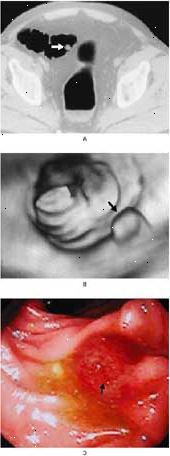

Εικονική κολονοσκόπηση είναι μια ασφαλής, μη επεμβατική τρόπος για να βρείτε πολυπόδων του παχέος εντέρου και άλλες ανωμαλίες. Η πιο εμπεριστατωμένη εξέταση για καρκίνο του παχέος εντέρου περιλαμβάνει ένα γιατρό που βλέπουν το σύνολο του παχέος εντέρου. Μια εικονική κολονοσκόπηση επιτρέπει οι γιατροί εξετάζουν το σύνολο του παχέος εντέρου για πολύποδες και οι καρκίνοι χρησιμοποιώντας ένα σαρωτή CT και λογισμικού εικονικής πραγματικότητας. Αυτό καθιστά λιγότερο επεμβατική από τις τυποποιημένες μεθόδους διαλογής. Συμβατική κολονοσκόπηση, για παράδειγμα, απαιτεί τη χρήση μιας μακράς οπτικού σωλήνα που εισάγεται μέσω του ορθού και του παχέος εντέρου. Και κλύσματα βαρίου μπορεί να είναι πολύ δυσάρεστη διαδικασία. Αν εικονική κολονοσκόπηση ενθαρρύνει περισσότερους ανθρώπους να προβληθούν, λένε οι ειδικοί, θα μπορούσε να σώσει χιλιάδες ζωές.

Σχετικά με την ημέρα της διαδικασίας, ο γιατρός τοποθετεί ένα μικρό, εύκαμπτο σωλήνα από καουτσούκ στο ορθό έντερο σας. Άνω και κάτω τελεία σας στη συνέχεια θα απαλά γεμίζουν με αέρα σε ένα επίπεδο που μπορεί να ανεχθεί. Ενώ βρίσκεστε στην πλάτη σας και στη συνέχεια στο στομάχι σας, ακτινολόγος θα λάβει μια αξονική τομογραφία της κοιλιάς σας.

Μια αξονική τομογραφία δημιουργεί λεπτομερείς εικόνες του παχέος εντέρου σε έναν υπολογιστή. Αυτές οι εικόνες επιτρέπουν στον ακτινολόγο να δείτε πολύποδες ή άλλες ανωμαλίες. Αν δεν υπάρχουν, δεν θα χρειαστεί άλλες διαδικασίες. Εάν ο γιατρός διαπιστώσει πολύποδες ή οι καρκίνοι, θα πρέπει να έχουν μια παραδοσιακή κολονοσκόπηση. Ο γιατρός μπορεί στη συνέχεια αφαίρεση των ιστών, που ονομάζεται βιοψία, και να μελετήσει κάτω από ένα μικροσκόπιο.